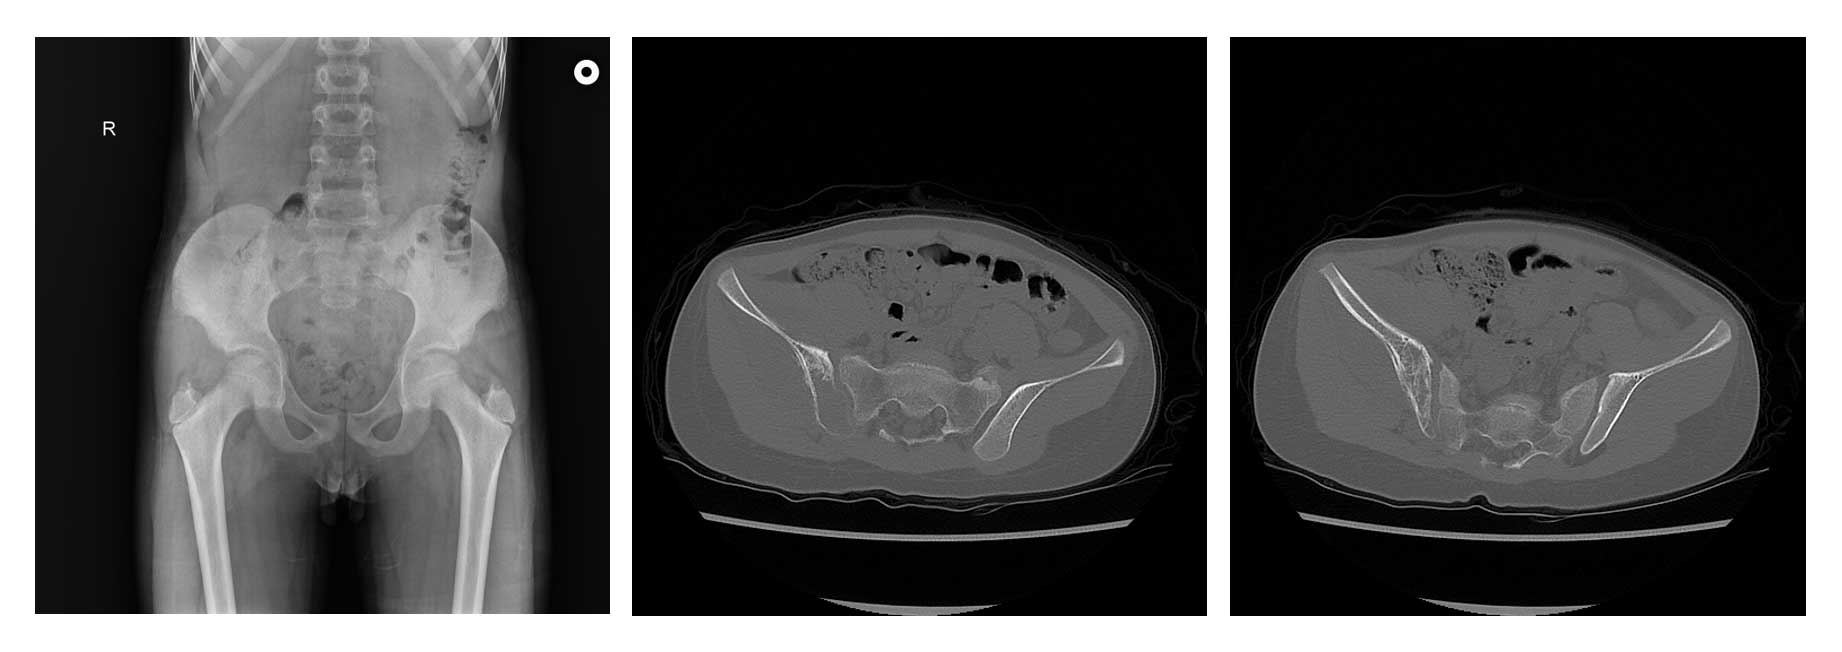

Ameliyat Öncesi: Röntgende sağ iliak kanatta düzensizlik, tomografide kemik harabiyeti ve periost reaksiyonu görülmekte.

Radyolojik tetkiklerde sağ iliak kanat yerleşimli kemik harabiyetine yol açan kitle saptandı.